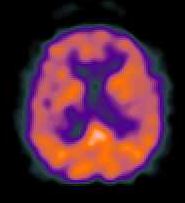

Pozytonowa tomografia emisyjna (PET): wykrywa wprowadzony do krwi promieniotwórczy znacznik (np. glukoza z węglem 11C) podlegający rozpadowi beta i wysyłający pozytony.

Pozytony anihilują z elektronami dając pary kwantów gamma, wykrywanych przez pary liczników wokół głowy.

Konieczny jest akcelerator do wytwarzania krótkotrwałych substancji promieniotwórczych, 11C, 18F, 15O, 13N.

Umożliwia obrazowanie przepływu krwi na bieżąco, wykrywanie ognisk padaczki, guzów mózgu, bardzo czuły na obecność śladowych ilości wybranych substancji (np. dopaminy).

Eksperymenty psychologiczne - zwiększona praca danego obszaru zwiększa zapotrzebowanie na energię = dopływ krwi.

PET po raz pierwszy pokazał lokalizację wielu funkcji psychicznych, stosowany w medycynie molekularnej.